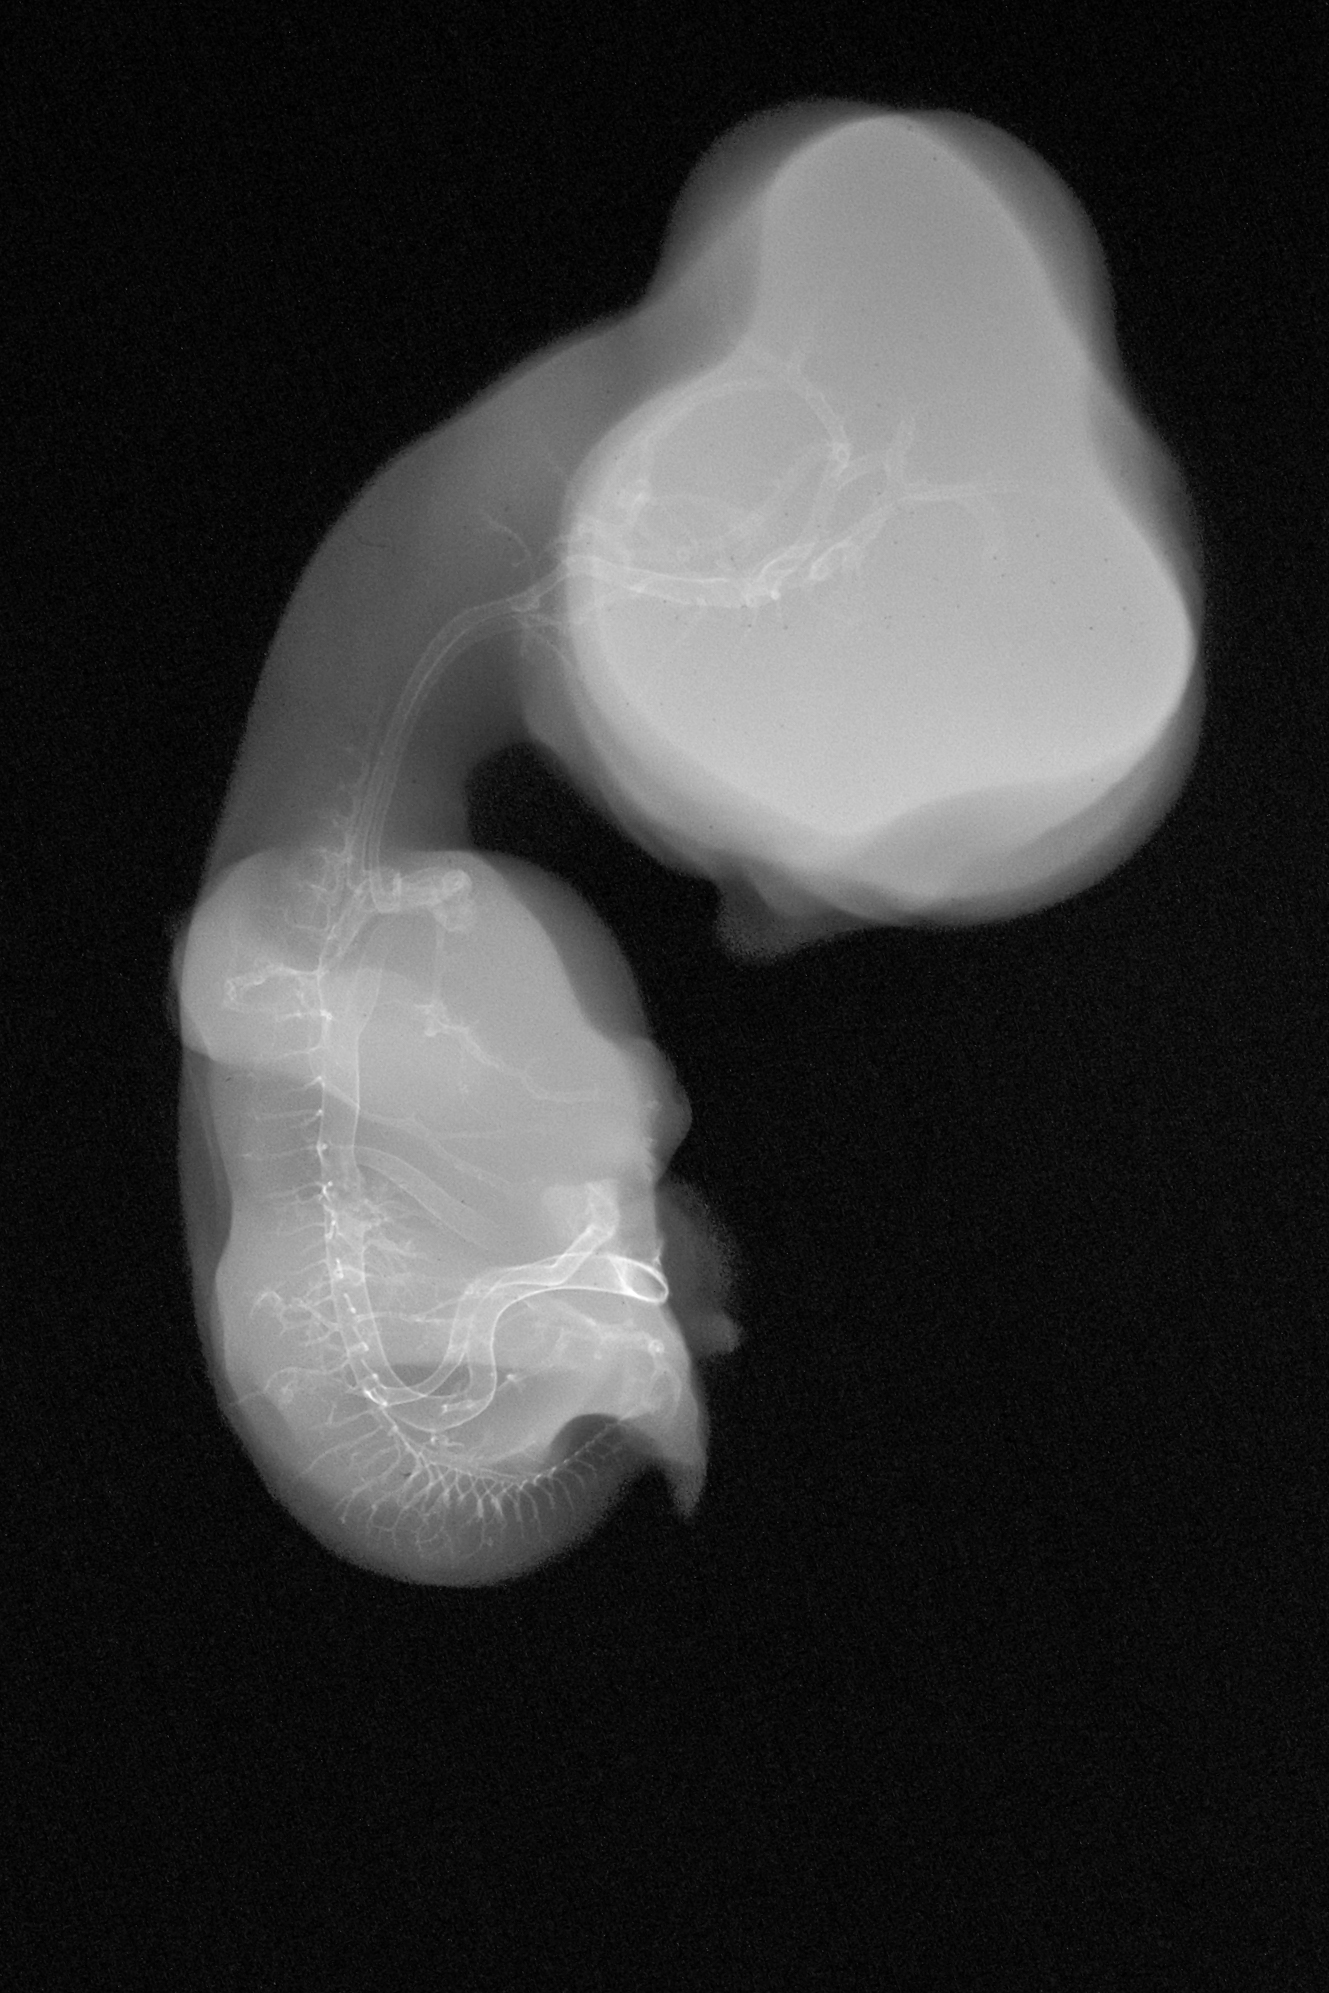

Chick Embryo Microangiography

Hamburger-Hamilton (HH) Stage 30 (approx. 6.5 days)

X-Ray Micrographs